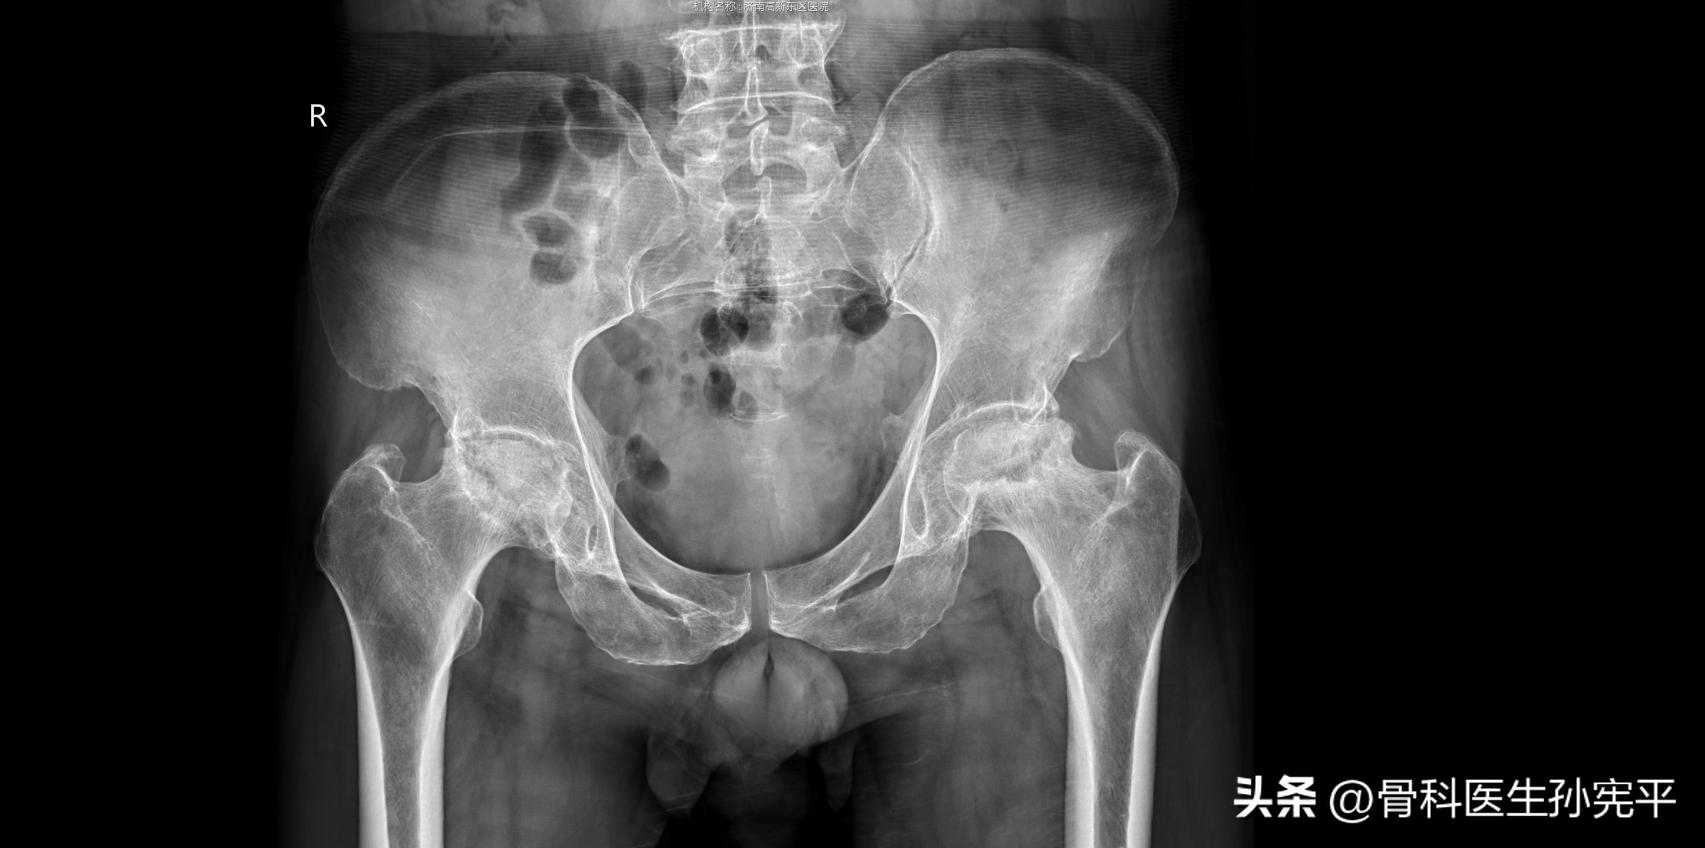

病例7:双臀部及大腿疼痛1年余。

双侧股骨头坏死

患者中年男性,1年多前开始出现双臀部、大腿外侧至膝关节疼痛,逐渐出现行走不利,于基层民营医院检查后给予针灸、理疗、敷药、口服药物等多种方式治疗,自述这1年看病人花了两三万,没确诊什么病。现症状逐渐加重,前来就诊,查体可见双下肢均外展受限,“4”字试验阳性。查骨盆片可见双侧股骨头坏死,股骨头失去正常形态,呈扁平、塌陷,密度不均,还是那句话,对于疾病的诊断认真查体是第一步!